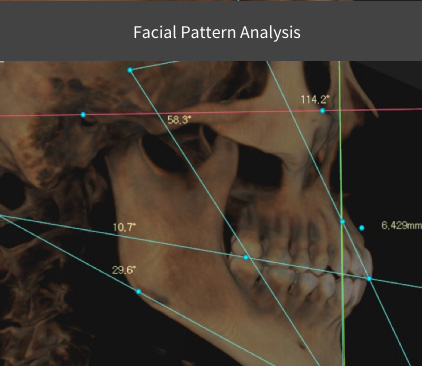

R2STUDIO™ + R2GATE® facial analysis

R2GATE® facial analysis: unique function that defines mid-facial plan, skeletal asymmetries, & esthetic problems

Facial Pattern Analysis

Built-in DOD program analyzes patient features & smile patterns as reference material for more complete results to increase patient satisfaction